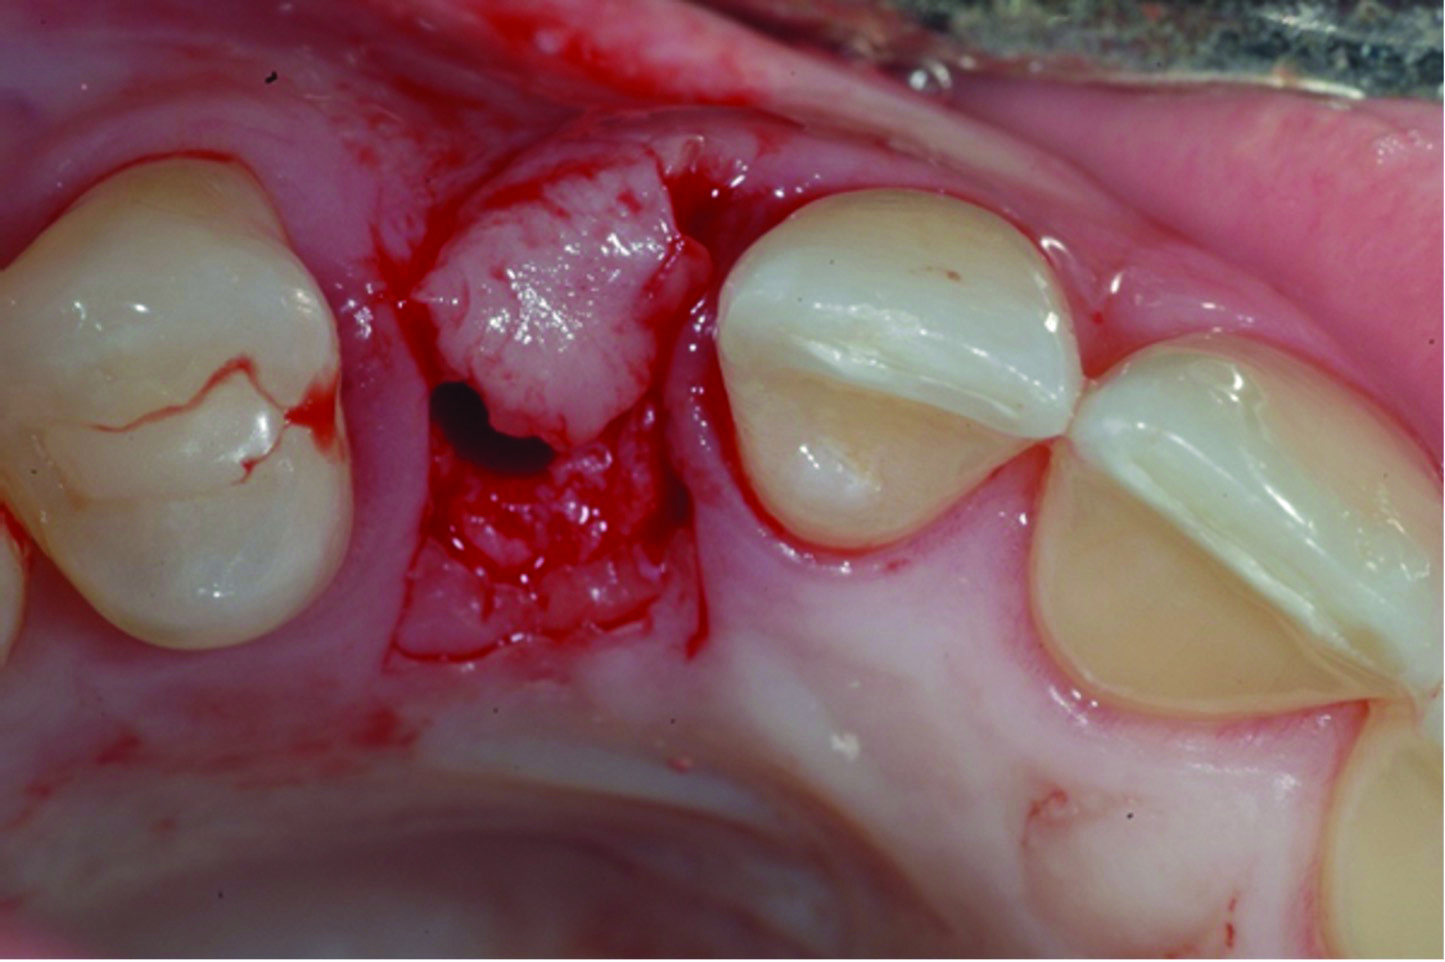

Fig 15 and Fig 16. Example of increasing MT with a CTG. Fig 15: buccal view of initial situation showing deficient mucosal thickness; Fig 16: occlusal view at implant placement with CTG.